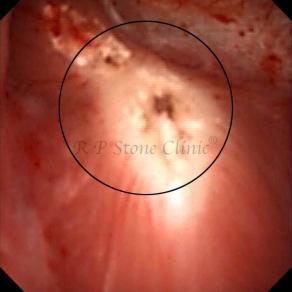

Kidney stone is a solid mass of CRYSTALS. It is the process of crystallization which initiates the formation of kidney stones. This happens in nephrons or units of kidney. Once a small crystal is formed, it can both grow & unite with other crystals leading to the formation of small concretion which eventually forms a stone. Once these large crystals detach from the collecting ducts, the process of stone formation starts in the renal collecting system. A recurrent kidney stone former is advised to know a little bit about something known as Randall’s plaque. Alexander Randall discovered plaques on the renal papillae eight decades back based on examination of 1154 pairs of autopsied Kidneys. He described these renal papillary lesions as cream colored or milk patch areas composed of calcium phosphate & calcium carbonate. These plaques could act as NIDUS for formation of KIDNEY STONE. Calcium Oxalate stone can form on this nidus & then detaches from this plaque to become a free floating stone in the collecting system of kidney

These images are taken as snap shots from the video recording of RIRS Surgery done at our hospital. These are Randall’s Plaques seen with Digital FLEX XC & Digital FLEX XC S. The cream or whitish patches are seen on the tips of RENAL PAPILLAE as seen in images below.